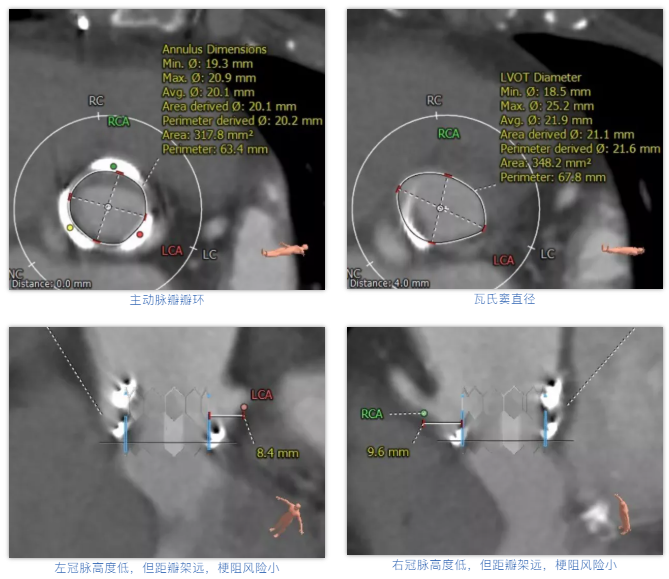

术前经详尽影像学重建和评估,该款人工生物瓣显影不理想,通过CT重建测量瓣环直径,评估冠脉梗阻风险。考虑到患者横位心,主动脉迂曲严重,最终选用经心尖入路,植入21# Renato球扩式瓣中瓣。手术顺利,瓣中瓣植入位置理想,功能表现出色,主动脉瓣峰值流速由术前3.4m/s下降至2.0m/s,平均跨瓣压差由术前32mmHg下降至8mmHg。经食道超声观察无瓣周漏及瓣中反流。

术前经详尽评估患者病情,通过CT重建测量瓣环直径、左室流出道面积。考虑到之前经房间隔入路外科换瓣,房间隔瘢痕严重,最终采用经心尖途径植入25# Renato球扩式瓣中瓣。手术顺利,瓣中瓣植入位置理想,功能表现出色,二尖瓣峰值流速由术前2m/s下降至1.4m/s,平均跨瓣压差由术前10mmHg下降至2mmHg,左室流出道压差正常,经食道超声观察无明显瓣中及瓣周返流。

术前经详尽影像学重建和评估,CT重建测量瓣环直径,评估冠脉梗阻风险及外周血管条件。最终采用经股动脉入路植入21# Renato球扩式瓣中瓣。手术顺利,瓣中瓣植入位置理想,功能表现出色,主动脉瓣峰值流速由术前4m/s下降至2m/s,平均跨瓣压差由术前40mmHg下降至6mmHg。经食道超声观察无瓣周漏及瓣中反流。